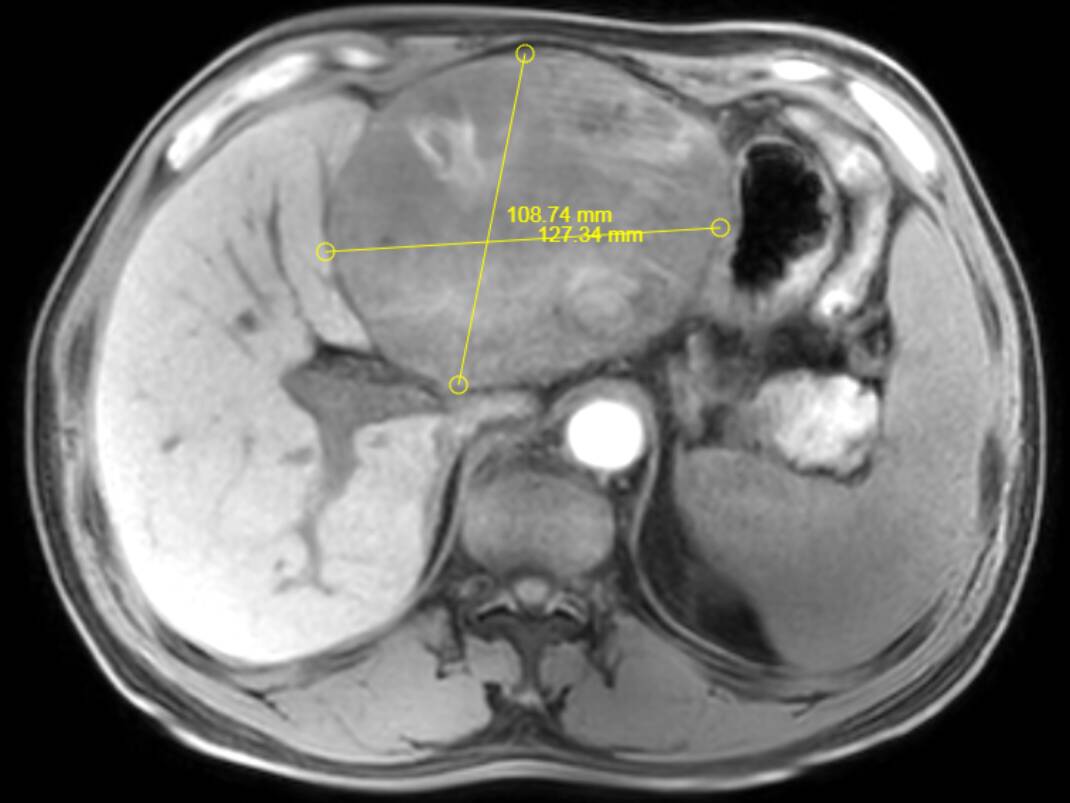

其中,成功为一名患者实施超大肝癌切除术,完整切除肿瘤大小达19cm×15cm,精准突破肝胆外科传统“手术禁区”,标志着普外二科在复杂肝胆肿瘤外科治疗领域迈上全新台阶。

此次切除的肿瘤体积巨大、血供丰富,与肝内重要血管、胆管粘连紧密,术中极易发生大出血、胆漏、肝功能衰竭等致命并发症。手术既要确保肿瘤完整根治、切缘干净,又要最大限度保留正常肝组织,难度与风险远超常规肝癌手术,对团队技术、经验与协作能力提出极高要求。

术前,科室联合影像、麻醉、重症监护、护理等多学科团队开展MDT会诊,全面评估肿瘤位置、大小、浸润范围及患者基础状况,精准规划切除路径与血管保护策略,反复推演手术流程,制定周密手术方案与应急预案,为手术成功筑牢坚实安全防线。

术中,手术团队在胡三元特聘专家与赵承乾科主任指导下,凭借精湛外科操作与丰富临床解剖经验,在高清手术视野下精细分离、逐层剥离、精准控切,妥善保护肝门部血管、胆管等关键结构,平稳完整剥离并切除巨大肿瘤,全程出血少、创伤可控,顺利完成高难度根治操作。